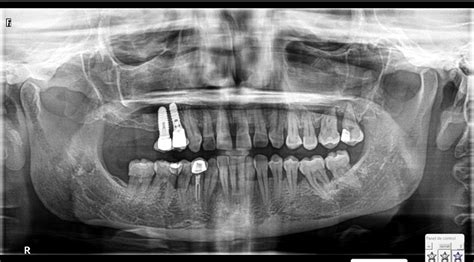

ANA MARÍA: Atrofia maxilar severa - Implantes cigomáticos y anteriores, regenereación ósea

La pérdida del hueso dental es una patología que se caracteriza por la disminución en la densidad y volumen óseo del hueso maxilar superior e inferior. Esta enfermedad se detecta a través de radiografías panorámicas y tomografías computarizadas en 3D. Las imágenes en 3D facilitan la identificación temprana de una baja densidad en el hueso alveolar.

El tratamiento de la atrofia maxilar severa requiere una evaluación y planificación cuidadosa por parte del equipo dental. Una evaluación clínica y radiográfica detallada es esencial para determinar la mejor estrategia de tratamiento.